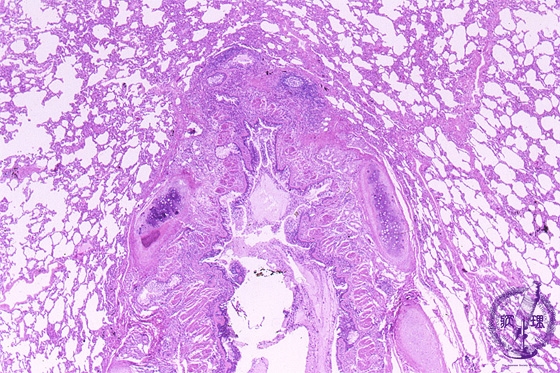

- 5.Lung, Pleura

- (6)Bronchial asthma

Microscopic view (HE stain, low power view): Bronchial wall smooth muscle (red arrow) proliferates with thickening of the entire bronchial wall. Mucus retention (blue arrow) is noted within the bronchial lumen.